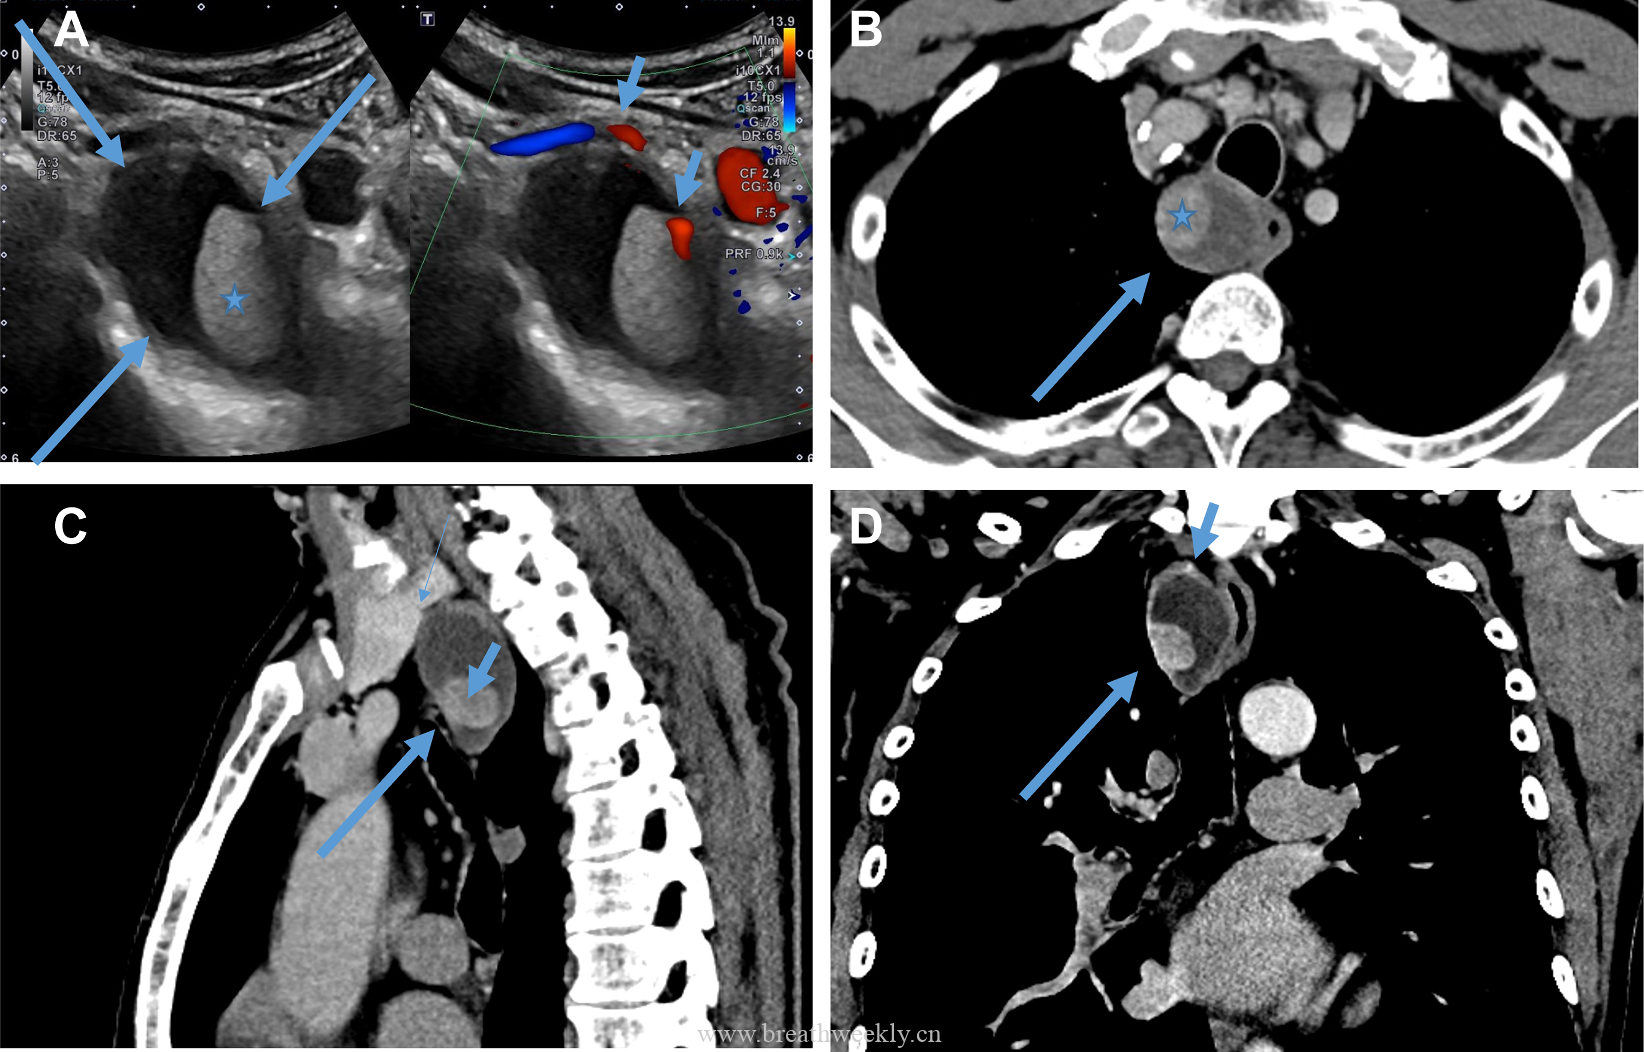

头颅CT除外颅内肿块及脑出血。脑及颈椎MRI(增强)除外CT隐性病灶,但发现右侧胸廓入口处囊性病灶。颈部超声及增强胸部CT:右侧上纵隔囊性占位,位于甲状腺右叶后下方,内见结节性实性成分及上极供血血管。胸部CT示前纵隔预期胸腺位置无异常软组织,提示胸腺脂肪萎缩。